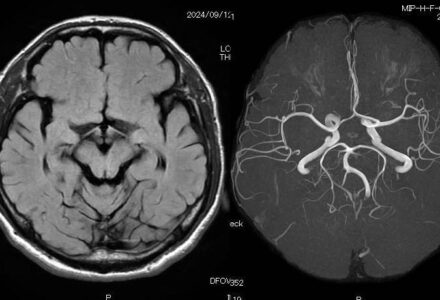

頭部MRI

MRIでわかる体のサイン ― 人間ドックでの活用

健康診断では血液検査やレントゲン検査が一般的ですが、近年はMRI(磁気共鳴画像)を用いた人間ドックも注目されています。MRIは強い磁場と電波を利用して...